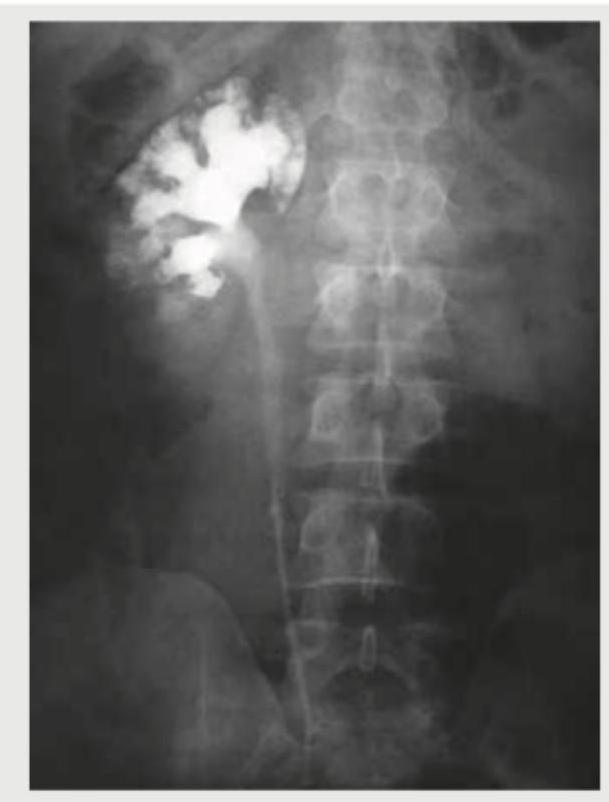

What is the radiological sign shown in the image?

Explanation: ***Adder head*** - The image displays an **intravenous pyelogram (IVP)**, and the "adder head" sign refers to the characteristic appearance of the dilated ureter and renal pelvis (renal collecting system) due to an **ureterocele**. - An **ureterocele** is a congenital dilatation of the distal part of the ureter as it enters the bladder, causing a filling defect and proximal hydronephrosis resembling a **snake's head** on an IVP. *Flower vase* - This is not a recognized radiological sign for the pathology shown. - The appearance of the collecting system, specifically the ureter proximal to the ureterocele, does not resemble a flower vase. *Spider leg* - The "spider leg" or "spidery" appearance is associated with **polyarteritis nodosa (PAN)** in renal angiography, where multiple microaneurysms and stenoses of small renal arteries give a spidery pattern. - The image here is an IVP showing the collecting system, not an angiogram of renal vessels. *Flower bouquet* - This is not a recognized radiological sign for the pathology shown. - The configuration of the collecting system in this IVP does not depict a flower bouquet.